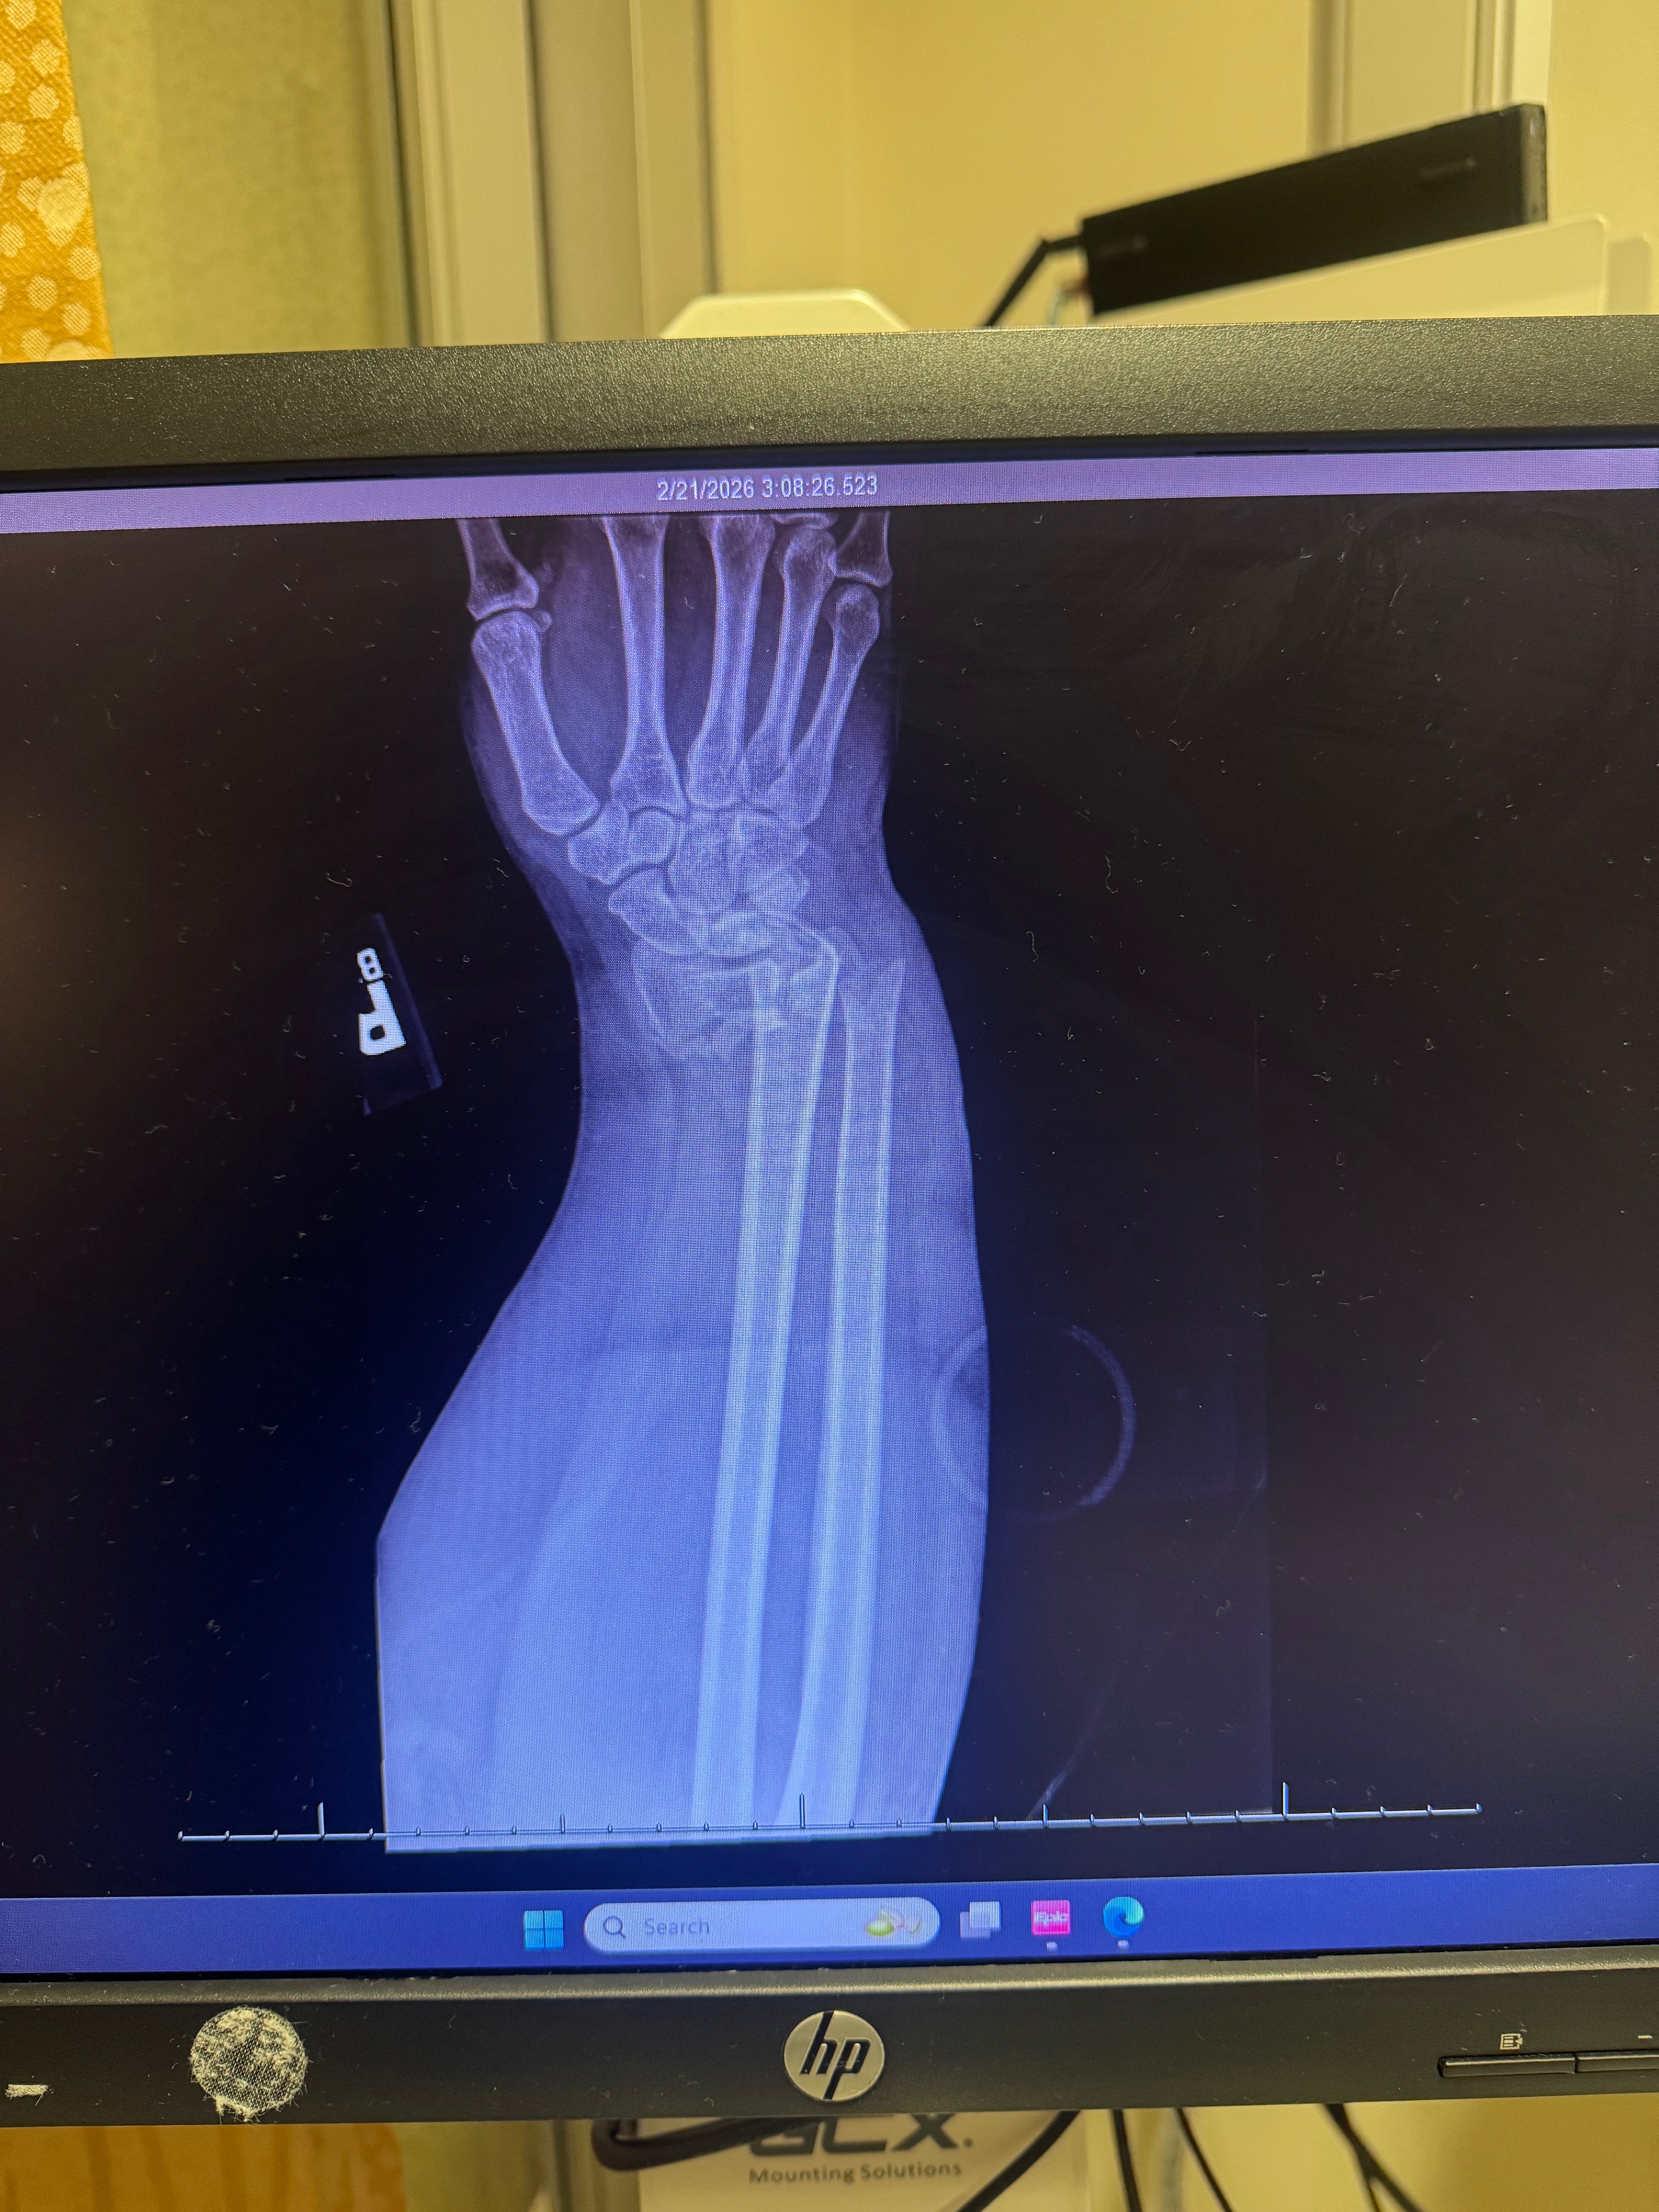

My name is Gabriella, and I’m reaching out because I recently experienced a serious accident. I had a bad fall that resulted in a broken wrist, and the injury was severe enough that I needed emergency surgery. Now, I’m facing a long road of intense physical therapy to regain full use of my hand.